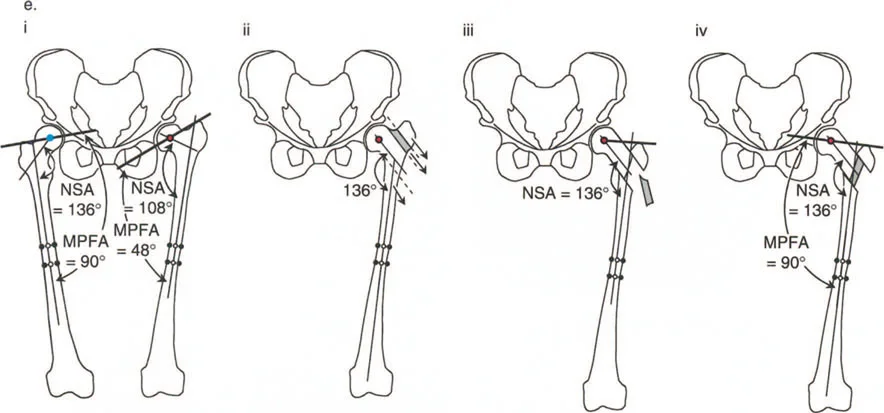

أ. قطع العظم الفحجي (Valgus Osteotomy)

- متى يستخدم: يُطبق عادة في حالات كسع الورك (Coxa Vara)، حيث تكون الزاوية بين عنق وجسم الفخذ صغيرة جدًا (أقل من 120 درجة)، مما يؤدي إلى قصر في الطرف وتضخم في المدور الكبير.

- الهدف: زيادة الزاوية بين عنق وجسم الفخذ إلى المعدل الطبيعي (125-135 درجة)، مما يطيل الطرف ويخفض المدور الكبير، ويحسن ذراع الرافعة للعضلات المبعدة للورك.

- التقنيات:

- طريقة واغنر (Wagner Osteotomy): وصفها واغنر عام 1978. تتضمن قطع عظم الفخذ تحت المدور (Subtrochanteric) مع نقل للمدور الكبير. هذا الإجراء يصحح كلاً من الزاوية بين عنق وجسم الفخذ (NSA) والزاوية الميكانيكية لعظم الفخذ القريب (MPFA) إلى الوضع الطبيعي. يتم تثبيت العظم بعد التصحيح عادةً بمثبت خارجي أو صفائح ومسامير.

* **طريقة مورشر (Morscher Osteotomy):** بديل لطريقة واغنر. تستعيد هذه الطريقة الزاوية بين عنق وجسم الفخذ عن طريق إجراء قطع عظم تحت المدور بالزاوية المطلوبة. يتم إطالة جسم الفخذ وتحريكه جانبيًا على طول ميل هذا القطع. يتم نقل المدور الكبير إلى الأسفل والجانب عن طريق إزالة أسطوانة عظمية من قاعدته ثم وضعها بين المدور وجسم الفخذ لملء الفراغ الجانبي. تصحح هذه الجراحة كلاً من الزاوية بين عنق وجسم الفخذ والزاوية الميكانيكية لعظم الفخذ القريب إلى الوضع الطبيعي. ومع ذلك، لا تغير هذه الطريقة اتجاه رأس الفخذ في التجويف الحقي، وإذا كان هذا التغيير مطلوبًا، تُفضل طريقة واغنر.

ب. قطع العظم الفاروسي (Varus Osteotomy)

- متى يستخدم: يُطبق في حالات فحج الورك (Coxa Valga)، حيث تكون الزاوية بين عنق وجسم الفخذ كبيرة جدًا، أو في حالات التهاب المفاصل التنكسي (الخشونة) لتحويل مناطق تحمل الوزن في المفصل، أو عندما يكون رأس الفخذ بيضاوي الشكل.

- الهدف: تقليل الزاوية بين عنق وجسم الفخذ، مما يزيد من ذراع الرافعة للعضلات المبعدة ويقلل الضغط على المفصل. قد يؤدي هذا إلى إزاحة المدور الكبير للأعلى، مما يستدعي إجراء نقل للمدور الكبير لتعويض هذا التأثير.

2. نقل المدور الكبير (Greater Trochanteric Transfer)

يعتبر نقل المدور الكبير إجراءً جراحيًا حيويًا، غالبًا ما يتم إجراؤه بالتزامن مع قطع عظم الفخذ، أو كإجراء منفصل في حالات معينة.

- متى يستخدم:

- لتعويض قصر ذراع الرافعة: في قطع العظم الفاروسي، قد ينتقل المدور الكبير للأعلى، مما يضعف العضلات المبعدة. نقل المدور للأسفل والجانب يعيد ذراع الرافعة.

- في حالات تضخم المدور الكبير (Overgrown Trochanter): خاصة عندما يكون المدور الكبير بارزًا بشكل مفرط، مما يسبب احتكاكًا أو ألمًا.

- لتحسين وظيفة العضلات المبعدة: في حالات ضعف العضلات المبعدة أو مشية ترندلنبورغ.

3. أمثلة سريرية وحالات خاصة

- الورك الفاروسي مع المدور الكبير المتضخم: في هذه الحالات، يكون التشوه ناتجًا جزئيًا عن عنق الفخذ وجزئيًا عن تضخم المدور. يتطلب التصحيح الجراحي عادةً قطع عظم فحجي (Valgus Osteotomy) مع نقل للمدور الكبير.

- تشوه فحجي مع دوران داخلي لعظم الفخذ القريب وخلع جزئي للورك: قد يتطلب هذا قطع عظم فاروسي مع إزاحة وسطية ونقل المدور الكبير للأسفل والجانب.

صور بالأشعة السينية لحالة فتاة تعاني من تشوه فحجي مع دوران داخلي وخلع جزئي، توضح التدخل الجراحي بقطع عظم فاروسي مع نقل المدور الكبير والتثبيت بمثبت خارجي، ثم النتيجة النهائية بعد التعافي.

- رأس الفخذ البيضاوي: في بعض حالات كسع الورك، قد يكون رأس الفخذ بيضاوي الشكل. يهدف قطع العظم الفحجي في هذه الحالات إلى جعل المحور الطويل للقطع البيضاوي أكثر أفقية لزيادة مساحة تحمل الوزن وتقليل الضغط على المفصل.

صور بالأشعة السينية لحالة كسع الورك مع رأس فخذ بيضاوي، توضح كيفية تصحيح اتجاه المحور البيضاوي بقطع عظم فحجي لتحسين توزيع الحمل.